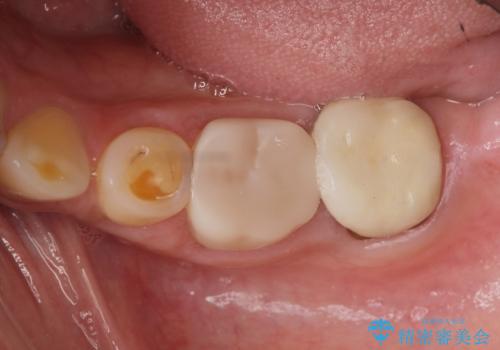

- 著しい歯ぎしりですり減ってしまった、奥歯のクラウンのやりかえを希望され来院されました。

このままの状態でクラウンのやりかえを行うと高さが低く安定の悪いクラウンとなってしまうため、事前に歯周外科手術を行い歯ぐきを下げることで安定性の高いクラウンを製作する治療計画としました。

長期にわたりに安定した環境に整えることで、長く使える可能性を高めることができます。